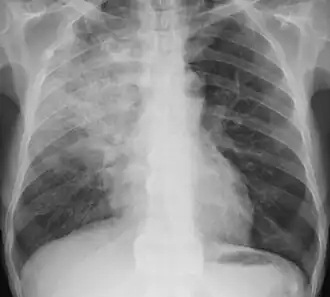

Chest x-ray of an adult with obstructive pneumonia in the right lung (left side of the image) evidenced by hypodense (less dark) area. This is from a blockage in the respiratory tract leading to an infection distal to the obstruction.

X-ray of focal pneumonia in lower right lung lobe (bottom left of chest in image) due to aspiration and airway obstruction.

Signs on x-ray that are more commonly seen than the object itself and can be indicative of foreign body aspiration include visualization of the foreign body or hyperinflation of the affected lung.[13] Other x-ray findings that can be seen with foreign body aspiration include obstructive emphysema, atelectasis, and consolidation.[8]